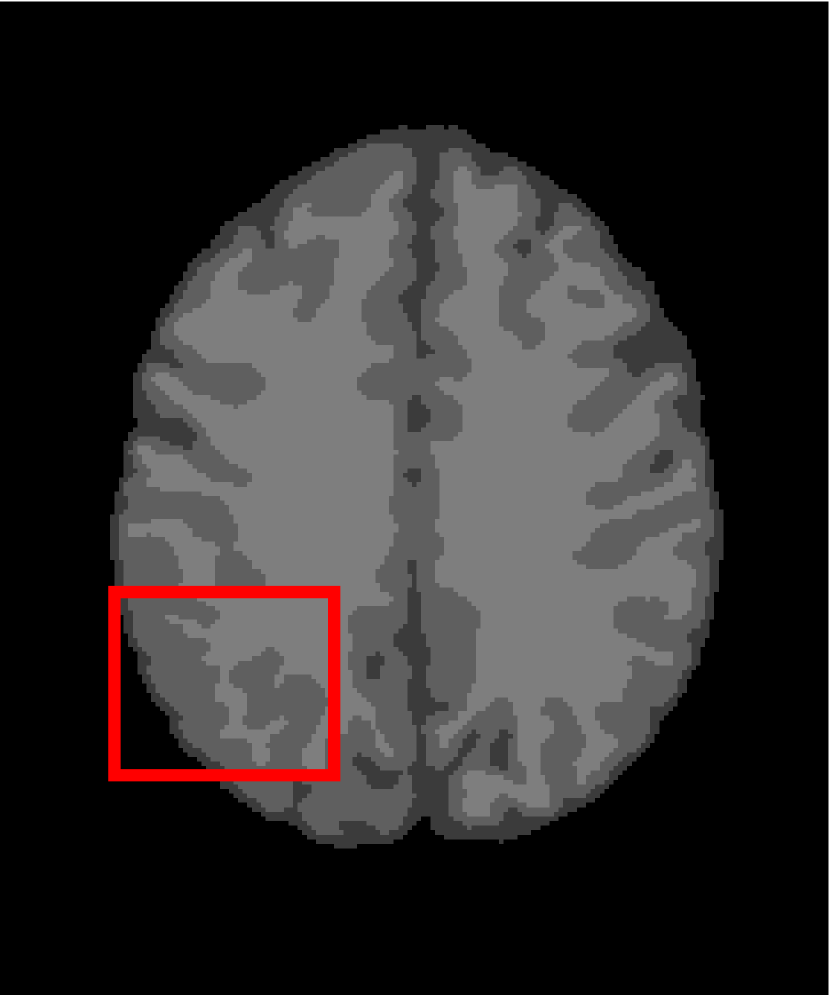

4.4.2 Results on Medical Images

Next, we representatively segment five medical images from BrianWeb. They are represented as five slices in the axial plane with a sequence of 70, 80, 90, 100 and 110, which are generated by T1 modality with slice thickness of 1mm resolution, 9% noise and 20% intensity non-uniformity. Here, we set c=4𝑐4c=4 for all cases. The comparison between WRFCM and its peers are shown in Fig. 9 and Table II. The best values are in bold.

Figure 9: Segmentation results on five medical images. The parameter: ϕ=5.35italic-ϕ5.35\phi=5.35. From top to bottom: noisy images, ground truth, and results of FCM_S1, FCM_S2, FLICM, KWFLICM, FRFCM, WFCM, DSFCM_N, and WRFCM.

TABLE II: Segmentation performance (%) on medical images in BrianWeb

Algorithm Fig. 9 column 1 Fig. 9 column 2 Fig. 9 column 3 Fig. 9 column 4 Fig. 9 column 5

SA SDS MCC SA SDS MCC SA SDS MCC SA SDS MCC SA SDS MCC

FCM_S1 75.756 97.852 96.225 75.026 98.109 96.656 79.792 98.452 97.334 81.887 98.614 97.680 81.869 94.254 90.947

FCM_S2 75.769 98.119 96.664 74.970 98.176 96.765 79.886 98.458 97.338 82.073 98.625 97.695 81.788 98.223 97.195

FLICM 74.998 98.070 96.568 74.185 98.122 96.660 79.099 98.515 97.432 81.447 98.627 97.691 81.668 98.273 97.260

KWFLICM 74.840 98.259 96.878 73.839 97.860 96.190 79.560 98.453 97.316 81.887 98.482 97.443 81.370 98.297 97.286

FRFCM 75.853 97.620 95.775 75.514 97.660 95.830 80.283 98.278 97.013 81.852 98.319 97.171 81.666 98.079 96.945

WFCM 75.507 97.124 94.957 74.471 97.213 95.045 79.316 97.845 96.283 81.358 97.546 95.211 81.452 95.247 92.501

DSFCM_N 76.400 92.325 86.262 75.288 91.574 85.095 79.861 97.678 95.996 81.831 93.304 88.829 81.750 94.302 91.024

WRFCM 82.317 98.966 98.147 82.141 98.298 96.970 83.914 98.963 98.202 83.533 99.170 98.603 84.615 98.429 97.511

By a view of the marked red square in Fig. 9, we find that FCM_S1, FCM_S2, FLICM, KWFLICM and DSFCM_N are vulnerable to noise and intensity non-uniformity. They give rise to the change of topological shapes to some extent. Unlike them, FRFCM and WFCM achieve sufficient noise removal. However, they produce overly smooth contours. Compared with its seven peers, WRFCM can not only suppress noise adequately but also acquire accurate contours. Moreover, it yields the visual result closer to ground truth than its peers. As Table II shows, WRFCM obtains optimal SA, SDS and MCC results for all five medical images. As a conclusion, it outperforms its peers visually and quantitatively.